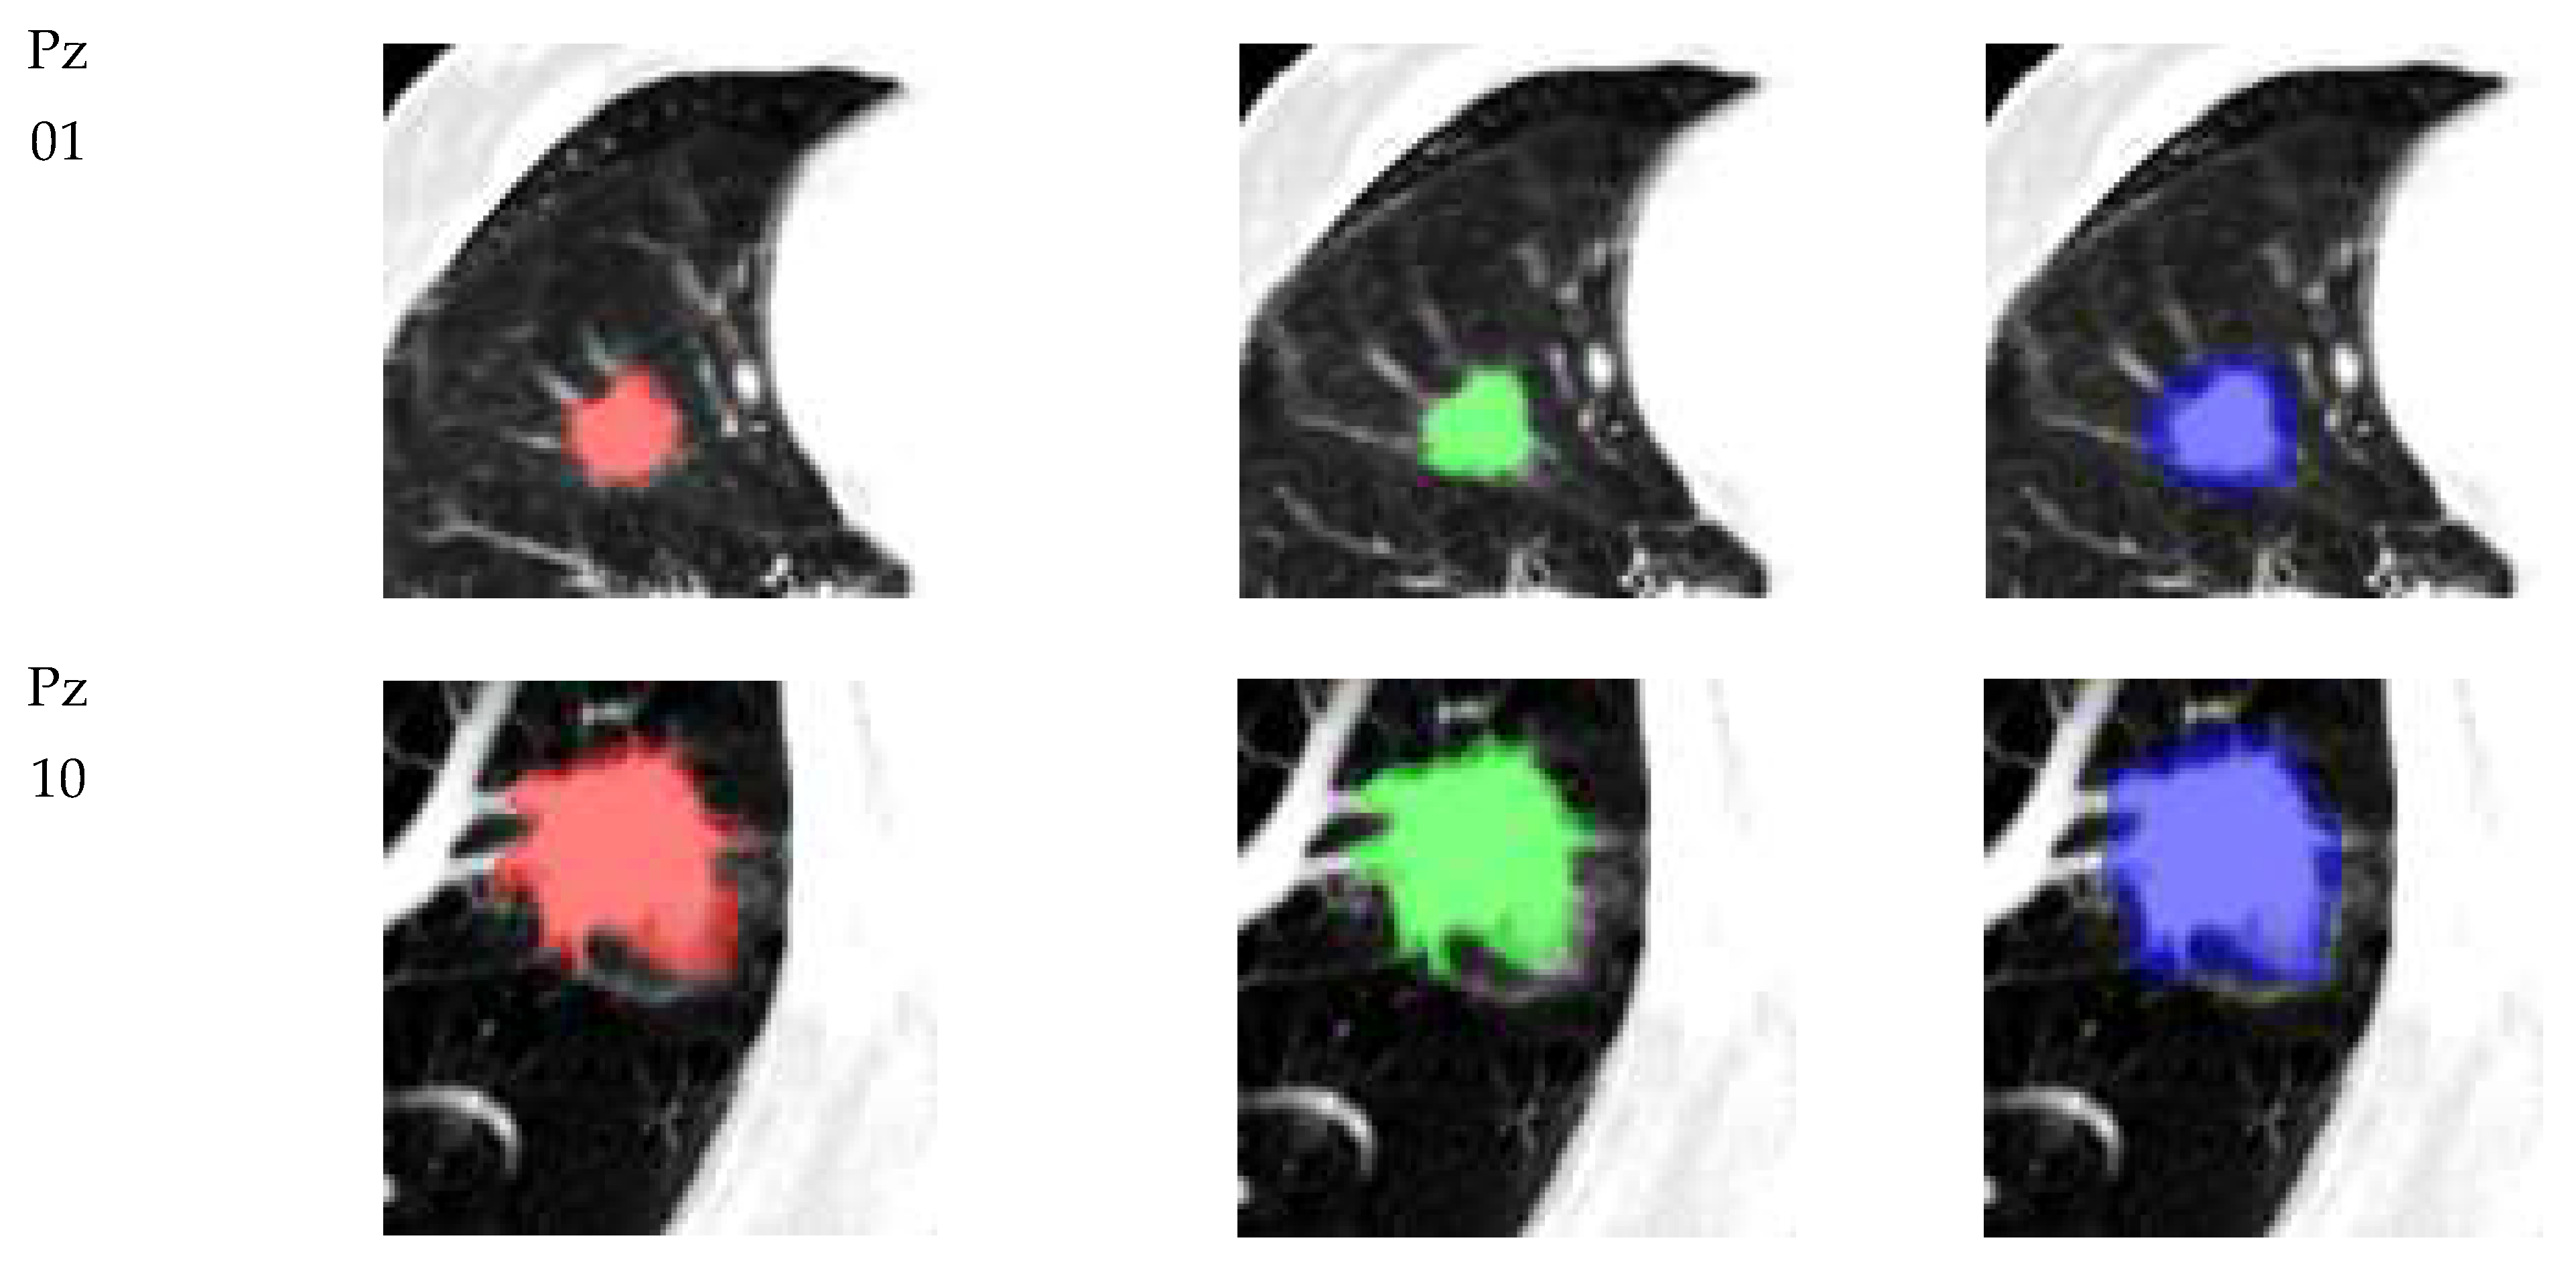

2.3. ROIs Delineation